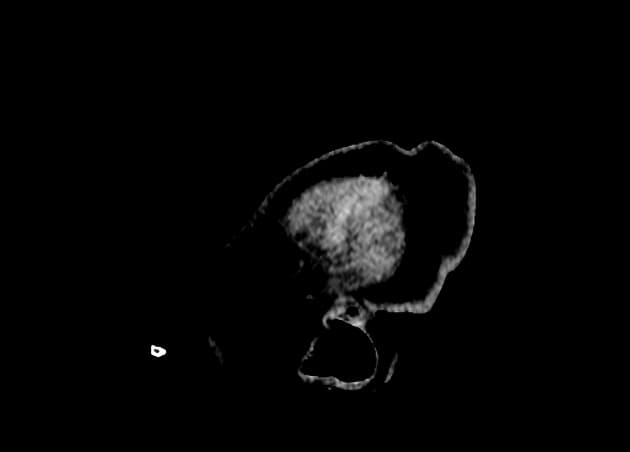

Axial T2

- Ghi nhận các vùng thay đổi tín hiệu hình bầu dục ở cầu nhạt (globi pallidi) hai bên, biểu hiện giảm tín hiệu trên T1 (low T1) và tăng tín hiệu trên T2 và FLAIR (high T2 and FLAIR signals).

- Các ổ (foci) nhỏ tương tự cũng được nhìn thấy ở nhân bèo sẫm (putamen) bên trái.

- "MRI thường cho thấy tín hiệu thấp trên T1 và tín hiệu cao trên T2/FLAIR tại các vùng nhân nền bị ảnh hưởng."